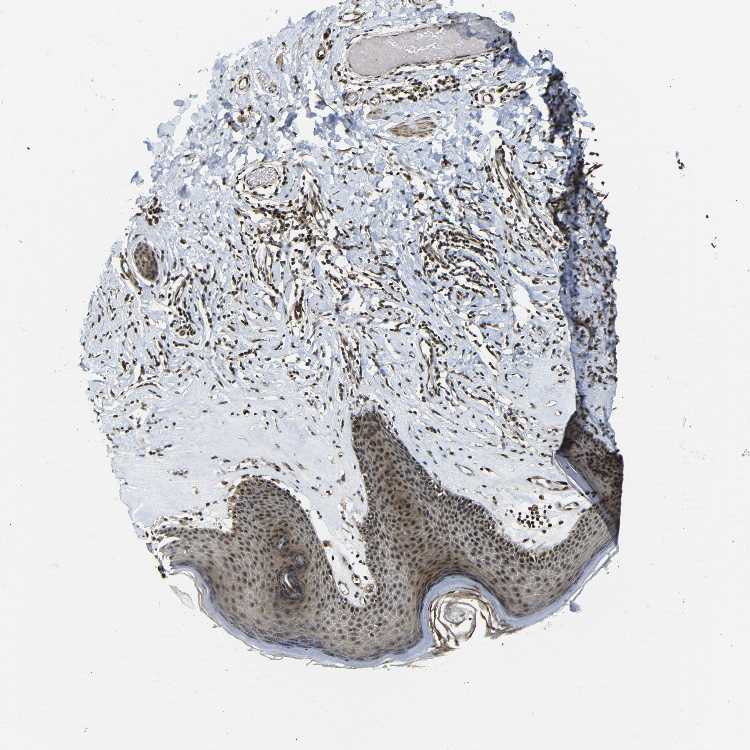

SKIN 1 - Antibody stainingi

Antibody staining in the annotated cell types in the current human tissue is reported as not detected, low, medium, or high, based on conventional immunohistochemistry profiling in selected tissues. This score is based on the combination of the staining intensity and fraction of stained cells.

Each image is clickable and will lead to virtual microscopy that enables deeper exploration of all samples and also displays staining intensity scores, fraction scores and subcellular localization as well as patient and tissue information for each sample.

Antibody HPA008586Antibody CAB013636

Langerhans HighLow

Fibroblasts MediumMedium

Keratinocytes HighMedium

Melanocytes HighLow

SKIN 2 - Antibody stainingi

Epidermal cells HighMedium